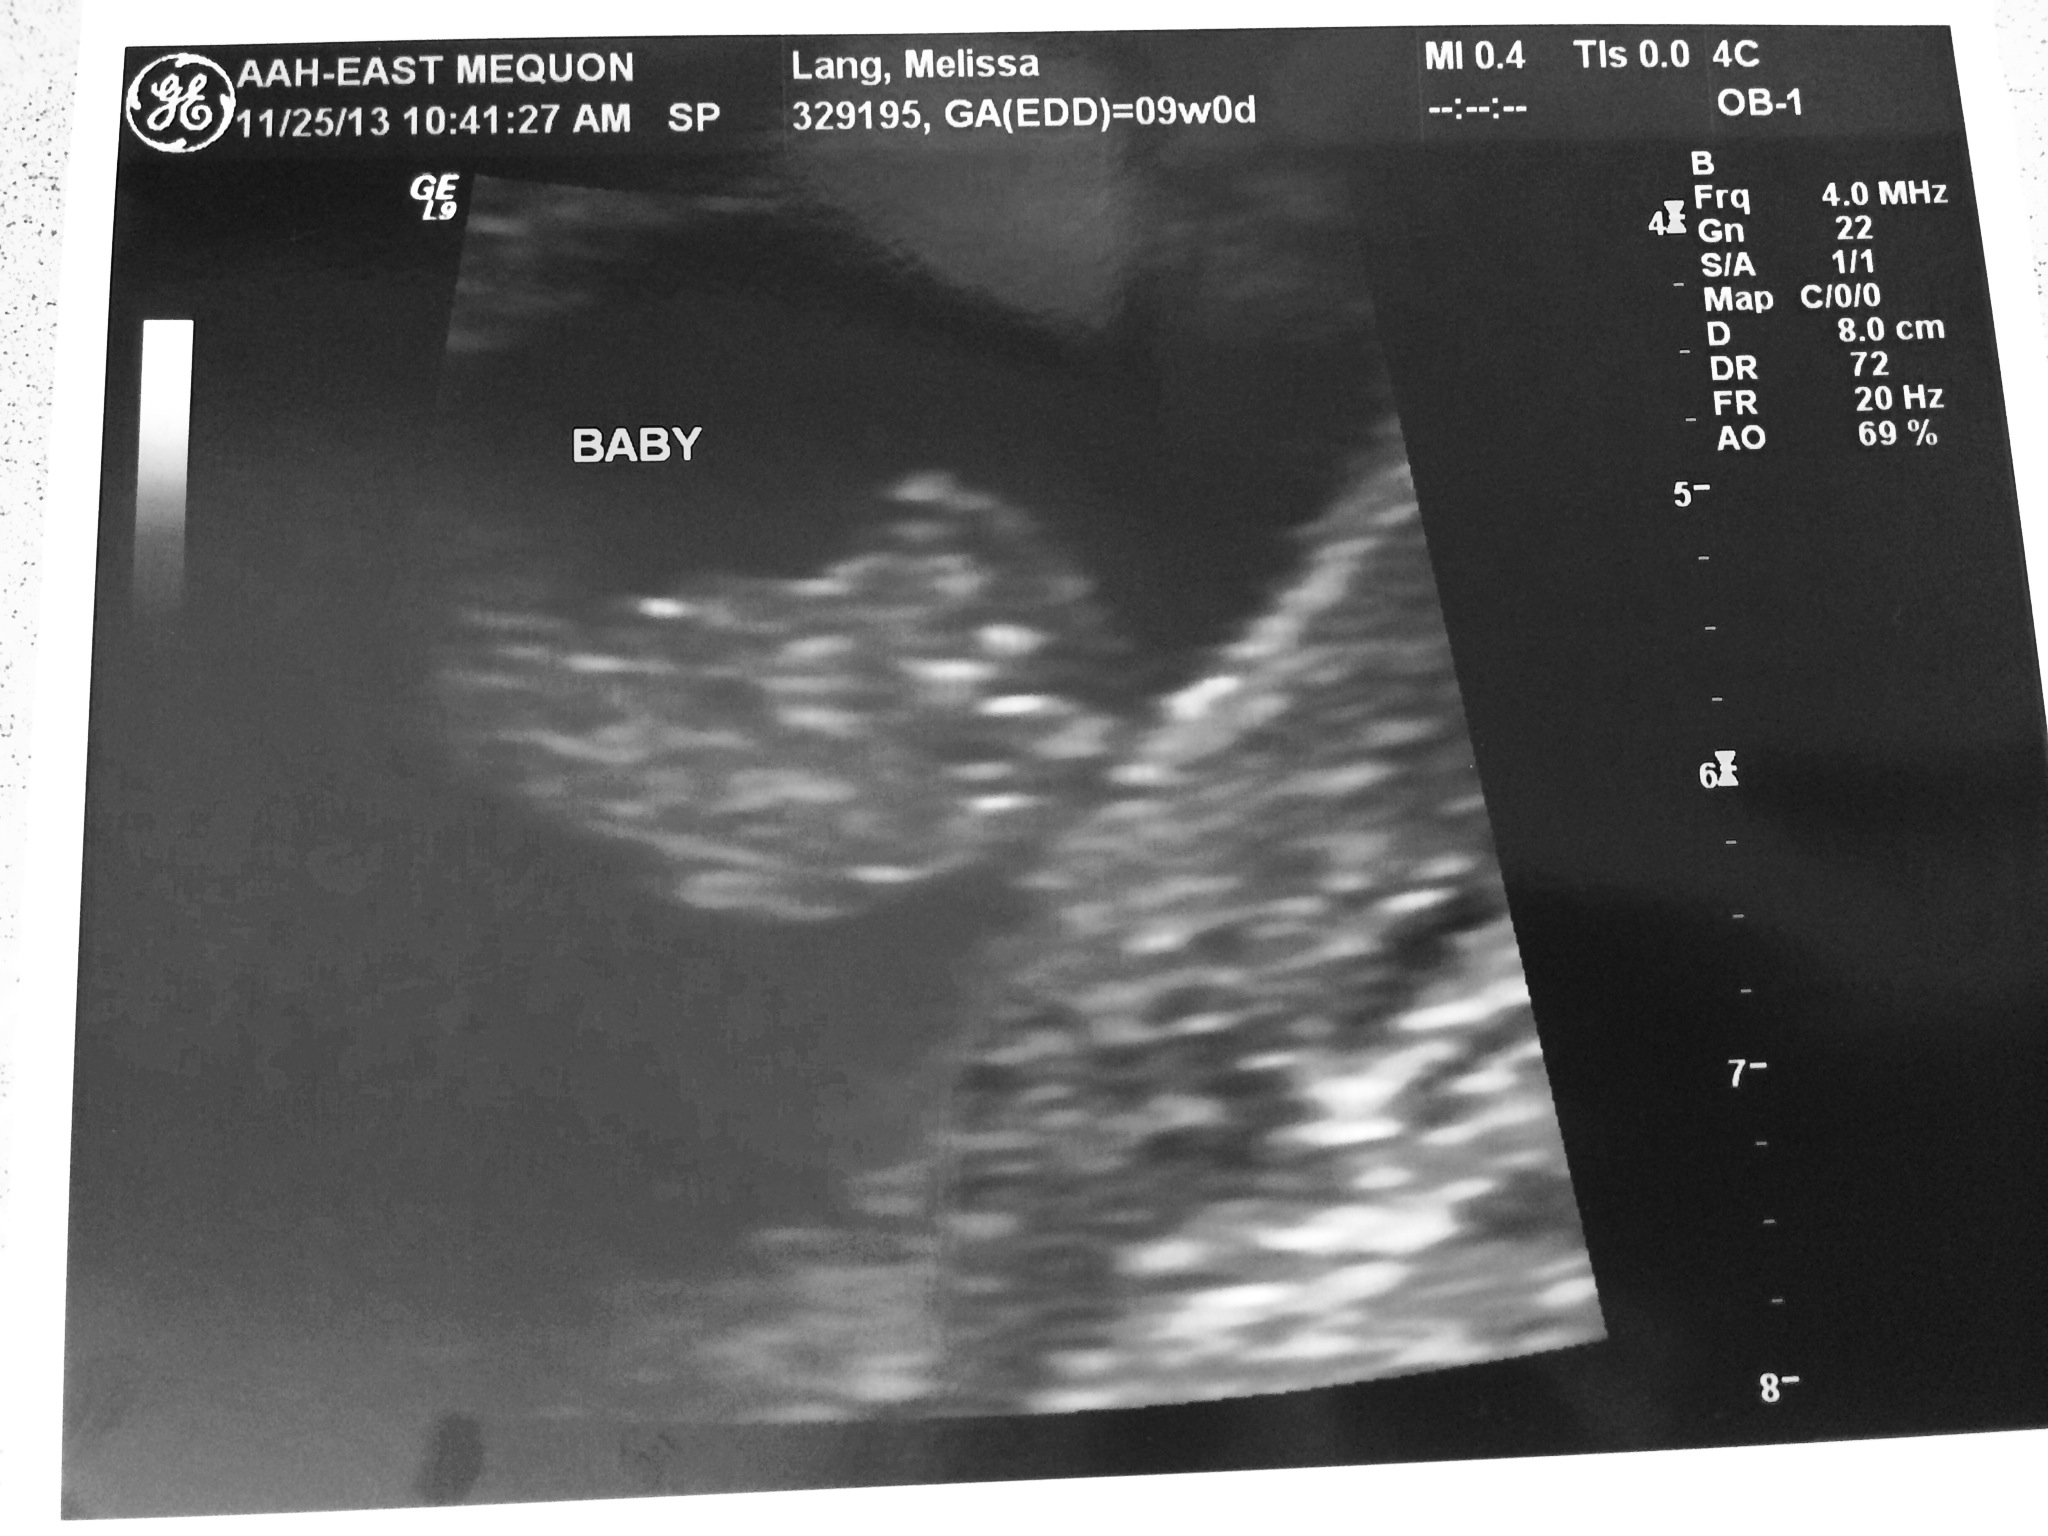

Today was our second ultrasound appointment, and my doctor’s way of appeasing my stubborn mind. As I’ve mentioned before, I was not convinced by the due date given at our last ultrasound appointment, so my doctor had suggested we do another one. Well, turns out the ultrasound tech and the fancy machinery is staying pretty consistent. My most recent due date was June 30th and today it was adjusted to June 27th. As I stated before, I am totally prepared to accept June 27th as the day and begin tracking the baby’s growth accordingly.

So, here’s where we’re at… I’m officially 9 weeks and 3 days pregnant, our baby is just over an inch from head to rump, and the heartbeat was 174 beats per minute.

It must be mentioned, that my mom is now convinced it’s going to be a girl! Only 10 more weeks until we find out! Also, I didn’t really see the heart beat last time, although my hubs did. This time, it was so clear and amazing to see. That little heart is working hard and was totally crazy and wonderful to be able to watch.

I’m not 100% sure, but I think we might have another ultrasound at 12 weeks for the nuchal screening. Can’t wait until the babe looks a little less like a blob and a little more like a sweet baby.